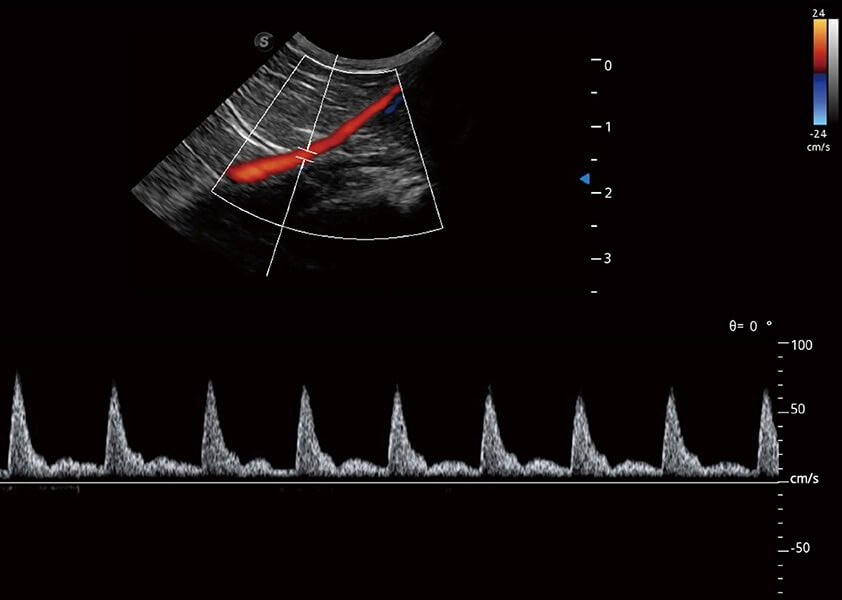

ProPet 60 作为一款高端台式动物超声设备,为动物医生的日常诊断提供了一系列贴合动物临床需求、解决临床实际问题的高级成像功能。凭借全系列高清探头,满足医生对腹部、心脏、生殖、浅表、肌骨等成像的所有需求,切实帮助您提升检查效率,提高诊断信心。

动物是人类最亲密的朋友和最值得信赖的伙伴。亚星官网也一直致力于探索动物专用的超声影像解决方案。 全新推出的ProPet系列,是亚星官网在动物超声影像智能化、专业化、精准化的一次跨越式革新。动物不能用言语来表述自己的不适,通过超声影像,ProPet系列搭建了动物医生与不同物种沟通的“桥梁”,为动物医生注入了“治愈之力”。